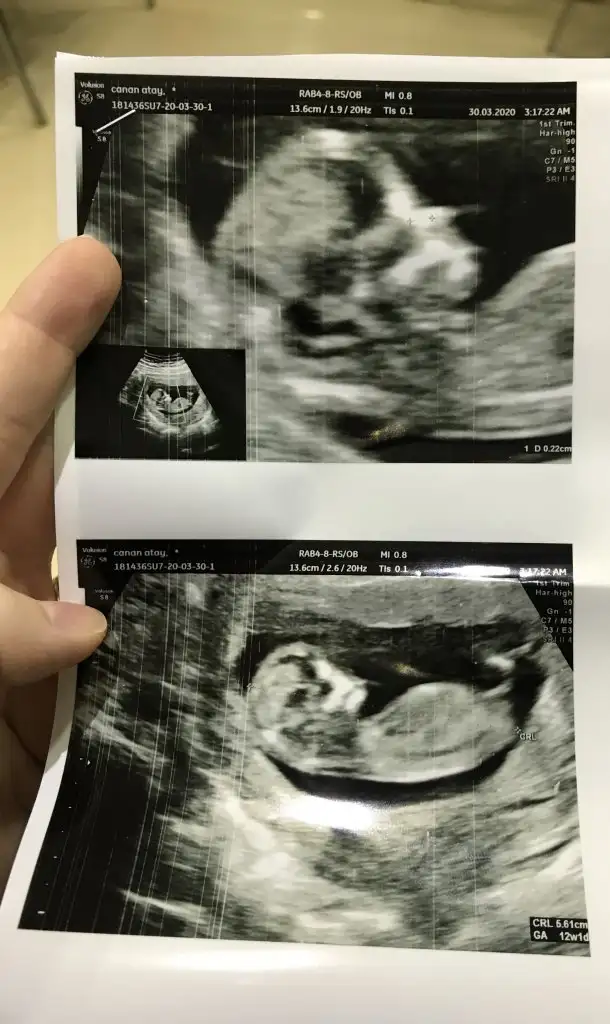

Meraba.12+1 iz cinsiyetini tahmin edebilirmisiniz

Buradaki fotoda 7 haftalıkken.karindan ultrason.bi önceki resimlerde doktor 12 haftalıkken kararsız kaldı.net birşey söyleyemedi.